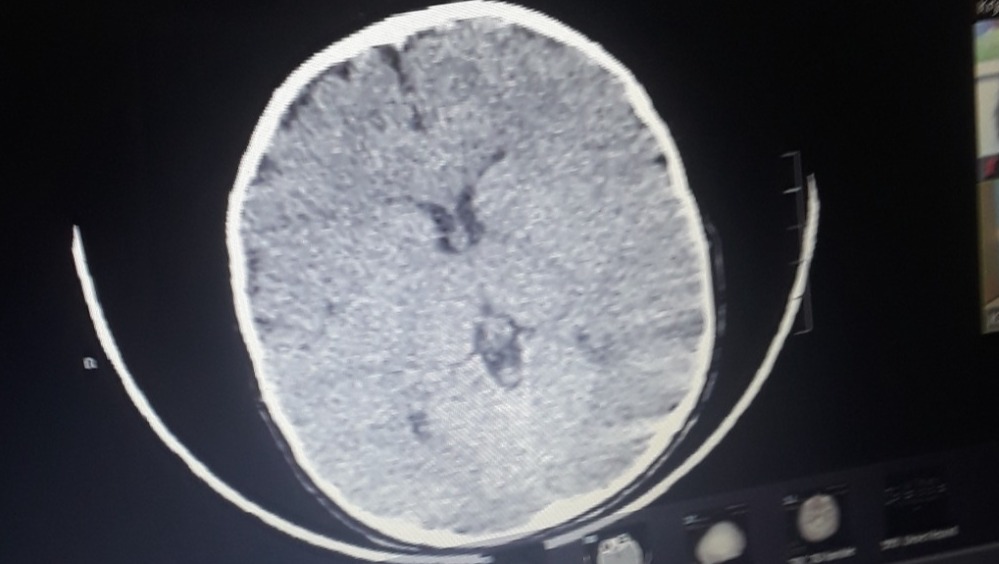

Our 15 month old Zoey LeeAnn was diagnosed with bicoronal craniosynostosis, and a simple doctor's appointment became a life changing event in the blink of an eye. After talking with the neurosurgeon and plastic surgeon we understand surgery is necessary. We find comfort in knowing God is with us  and that he gave us the very best team available Stanford has the very best facilities and doctors around. There are so many obstacles ahead that we are not prepared for. Knowing we are in the best of hands makes it a little bit easier . Zoey will be having surgery on December 17th at Lucile Packard childrens hospital at Stanford in Palo Altos California. Zoey will have pre-op appointments with her neurosurgeon plastic surgeon and the anesthesiologist on December 14th meaning we will need to fly out to California from Reno Nevada on the 12th or 13th of December. Her surgery is scheduled for the 17th and with the recovery time we believe we will be home around December 28th . We know the holidays are coming up and it's been a hard year for everybody but we are humbly asking for monetary donations to help with the costs of out of state travel, stay, food, and any unexpected cost during Zoeys surgery. Please if possible please help ease the financial stress, and allow us to focus on Zoeys surgery and recovery. And please please pray for Zoey LeeAnn she is our sweet sunflowers  brightening the day of everyone she meets. We love you Zoey LeeAnn.